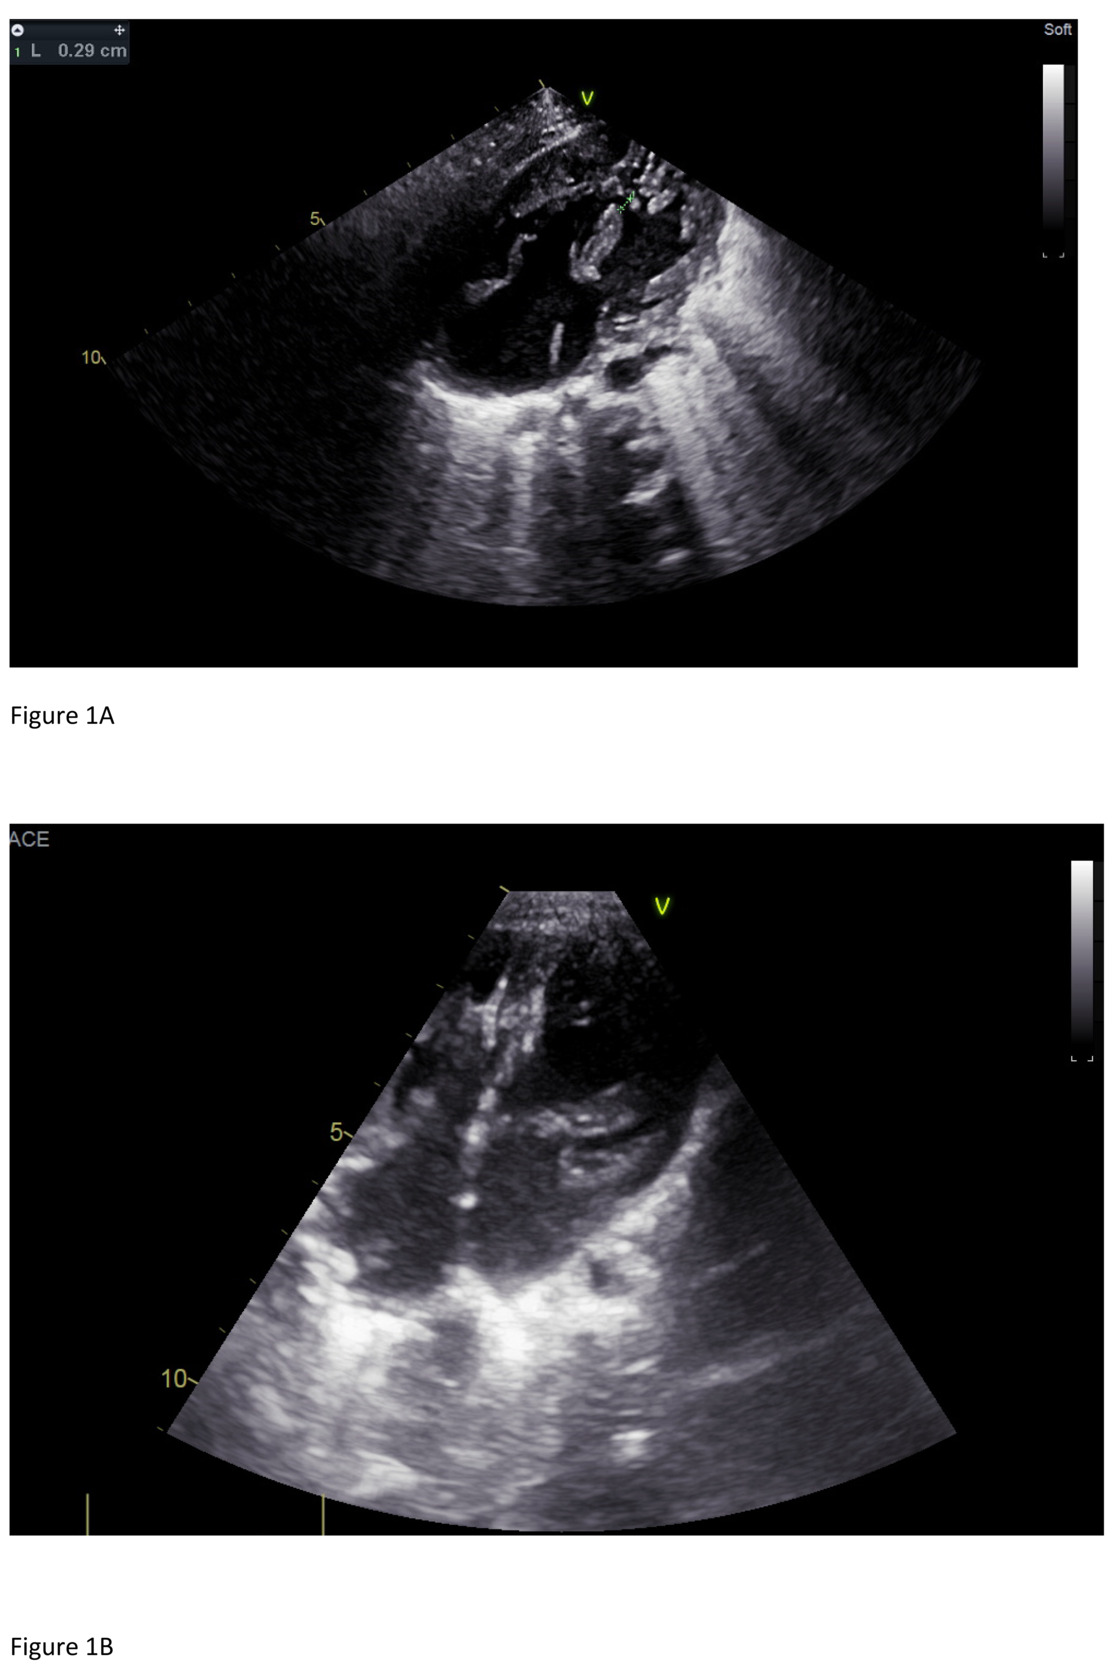

At 20 days of age, he started to have episodes of tachypnea and diaphoresis during feeding. On day 26 of life, he underwent pulmonary artery banding. The postoperative echocardiogram showed common atrioventricular canal type A, loose pulmonary artery banding with a mean pressure gradient (PG) of 17.5 mmHg (Figure 1A), a large mid- muscular ventricular septal defect measuring 5.8–6.7 mm with bilateral flow, a small inlet ventricular septal defects measuring 2 mm, a large ostium primum atrial septal defect, and a large ostium secundum atrial septal defect. There was difficulty weaning him off the ventilator and he required inotropic support. Therefore, on day 38 of life he underwent cardiac catheterization (Supplementary Material 2). The procedure revealed the following: